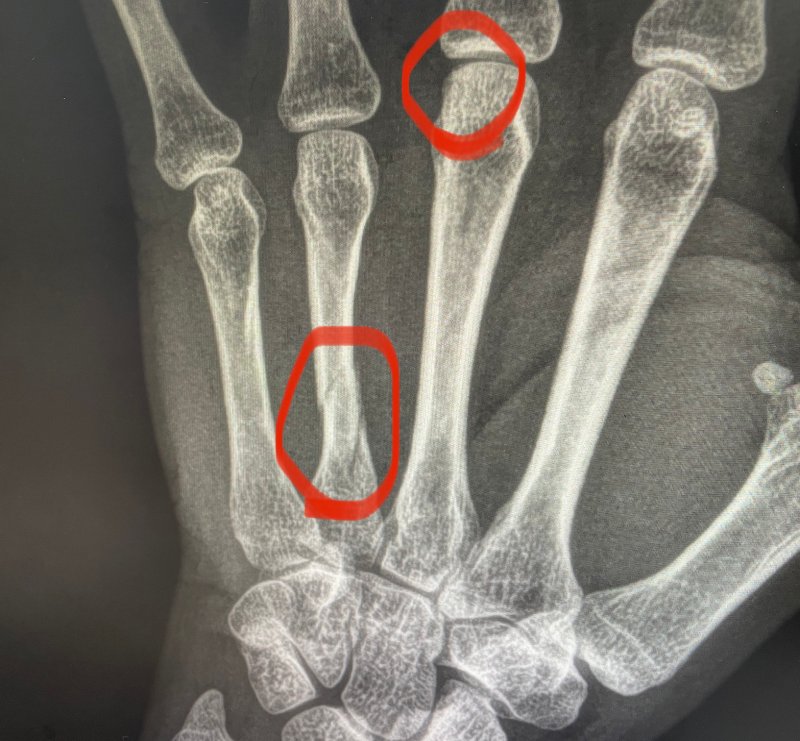

중수골은 손등에 있는 가장 긴 뼈 중에 하나입니다. 중수골 골절은 의외로 연령에 상관없이 많은 사람들이 생활하면서 겪을 수 있는 골절 중 하나입니다. 중수골 골절은 복서 골절로 많이 불리는 골절입니다. 대체로 5번 중수골의 골절이 가장 흔합니다. 저는 줄다리기하다가 중수골 골절이 되었습니다.

가장 먼저 손에 골절이 생기면 손을 스스로 움직일 수 없습니다. 혹시나 손이 스스로 움직여지더라도 뼈가 어긋나지 않게 움직일 수 없도록 고정을 하야합니다. 손이 슬슬 부어오르고 멍이 올라오는데 구할 수 있는 차가운 것으로 찜질을 해서 통증과 붓기, 염증을 완화시켜줘야 합니다. 그리고 바로 응급실에 가서 처치를 받아야 합니다. 저는 뼈가 많이 어긋나서 핀 고정술을 하기로 했습니다.

수술 약 4시간 정도 걸렸고 3일 입원 후 퇴원했습니다. 작은 핀 3개로 중수골을 고정하는 수술을 하였습니다. 실밥을 풀고 난 뒤 수술 부위의 딱지가 완전히 떨어지면 본격적인 상처 관리가 시작됩니다.